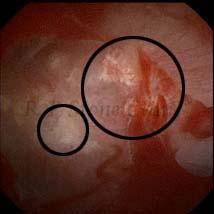

Kidney stone is a solid mass of CRYSTALS. It is the process of crystallization which initiates the formation of kidney stones. This happens in nephrons or units of kidney. Once a small crystal is formed, it can both grow & unite with other crystals leading to the formation of small concretion which eventually forms a stone. Once these large crystals detach from the collecting ducts, the process of stone formation starts in the renal collecting system. A recurrent kidney stone former is advised to know a little bit about something known as Randall’s plaque. Alexander Randall discovered plaques on the renal papillae eight decades back based on examination of 1154 pairs of autopsied Kidneys. He described these renal papillary lesions as cream colored or milk patch areas composed of calcium phosphate & calcium carbonate. These plaques could act as NIDUS for formation of KIDNEY STONE. Calcium Oxalate stone can form on this nidus & then detaches from this plaque to become a free floating stone in the collecting system of kidney

These images are taken as snap shots from the video recording of RIRS Surgery done at our hospital. These are Randall’s Plaques seen with Digital FLEX XC & Digital FLEX XC S. The cream or whitish patches are seen on the tips of RENAL PAPILLAE as seen in images below.

Randall’s Plaques may lead to the formation of Stones.

Those kidney stone patients who have Randall’s Plaques in their kidneys are more likely to form stones again (Recurrent Stones).

Stone Patients in whom Randall’s Plaques are detected at the time of RIRS Surgery should undergo regular ultrasound examination for early detection of stones.